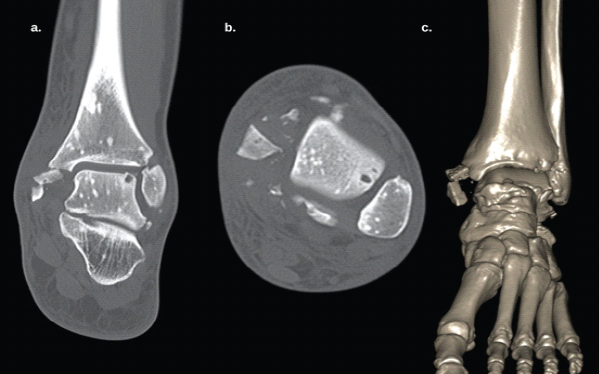

The ankle was immobilized in a neutral dorsiflexion position using a backslab, and the patient was admitted for further evaluation and surgical planning. During hospitalization, an extensive evaluation showed no associated conditions, skin lesions, or signs of endocrine dysfunction. Laboratory tests, including electrolytes, hematology, and urinalysis, were all within normal ranges. Thyroid and parathyroid hormones were normal. Vitamin D was decreased to 17 ng/mL. X-rays of other limbs showed similar well-defined sclerotic lesions in the distal radius and carpal bones (Fig. 2). CT scan of the ankle showed well-defined hyperintense foci in the cancellous bone of the distal tibia, consistent with OPK (Fig. 3).

Figure 3: (a) Coronal computed tomography (CT) scan of the left ankle showing multiple well-defined, symmetrically distributed, spherical/oval radiopaque lesions in the distal tibia, fibula, and talus, without bony architectural disruption. A comminuted medial malleolus fracture is also visible. (b) Axial CT showing similar findings in the fibula and talus. (C) 3D CT reconstruction.

The case was reviewed with the hospital’s bone tumor team. Based on clinical examination, normal laboratories, and imaging findings, a diagnosis of OPK was confirmed, and no further studies were deemed necessary.